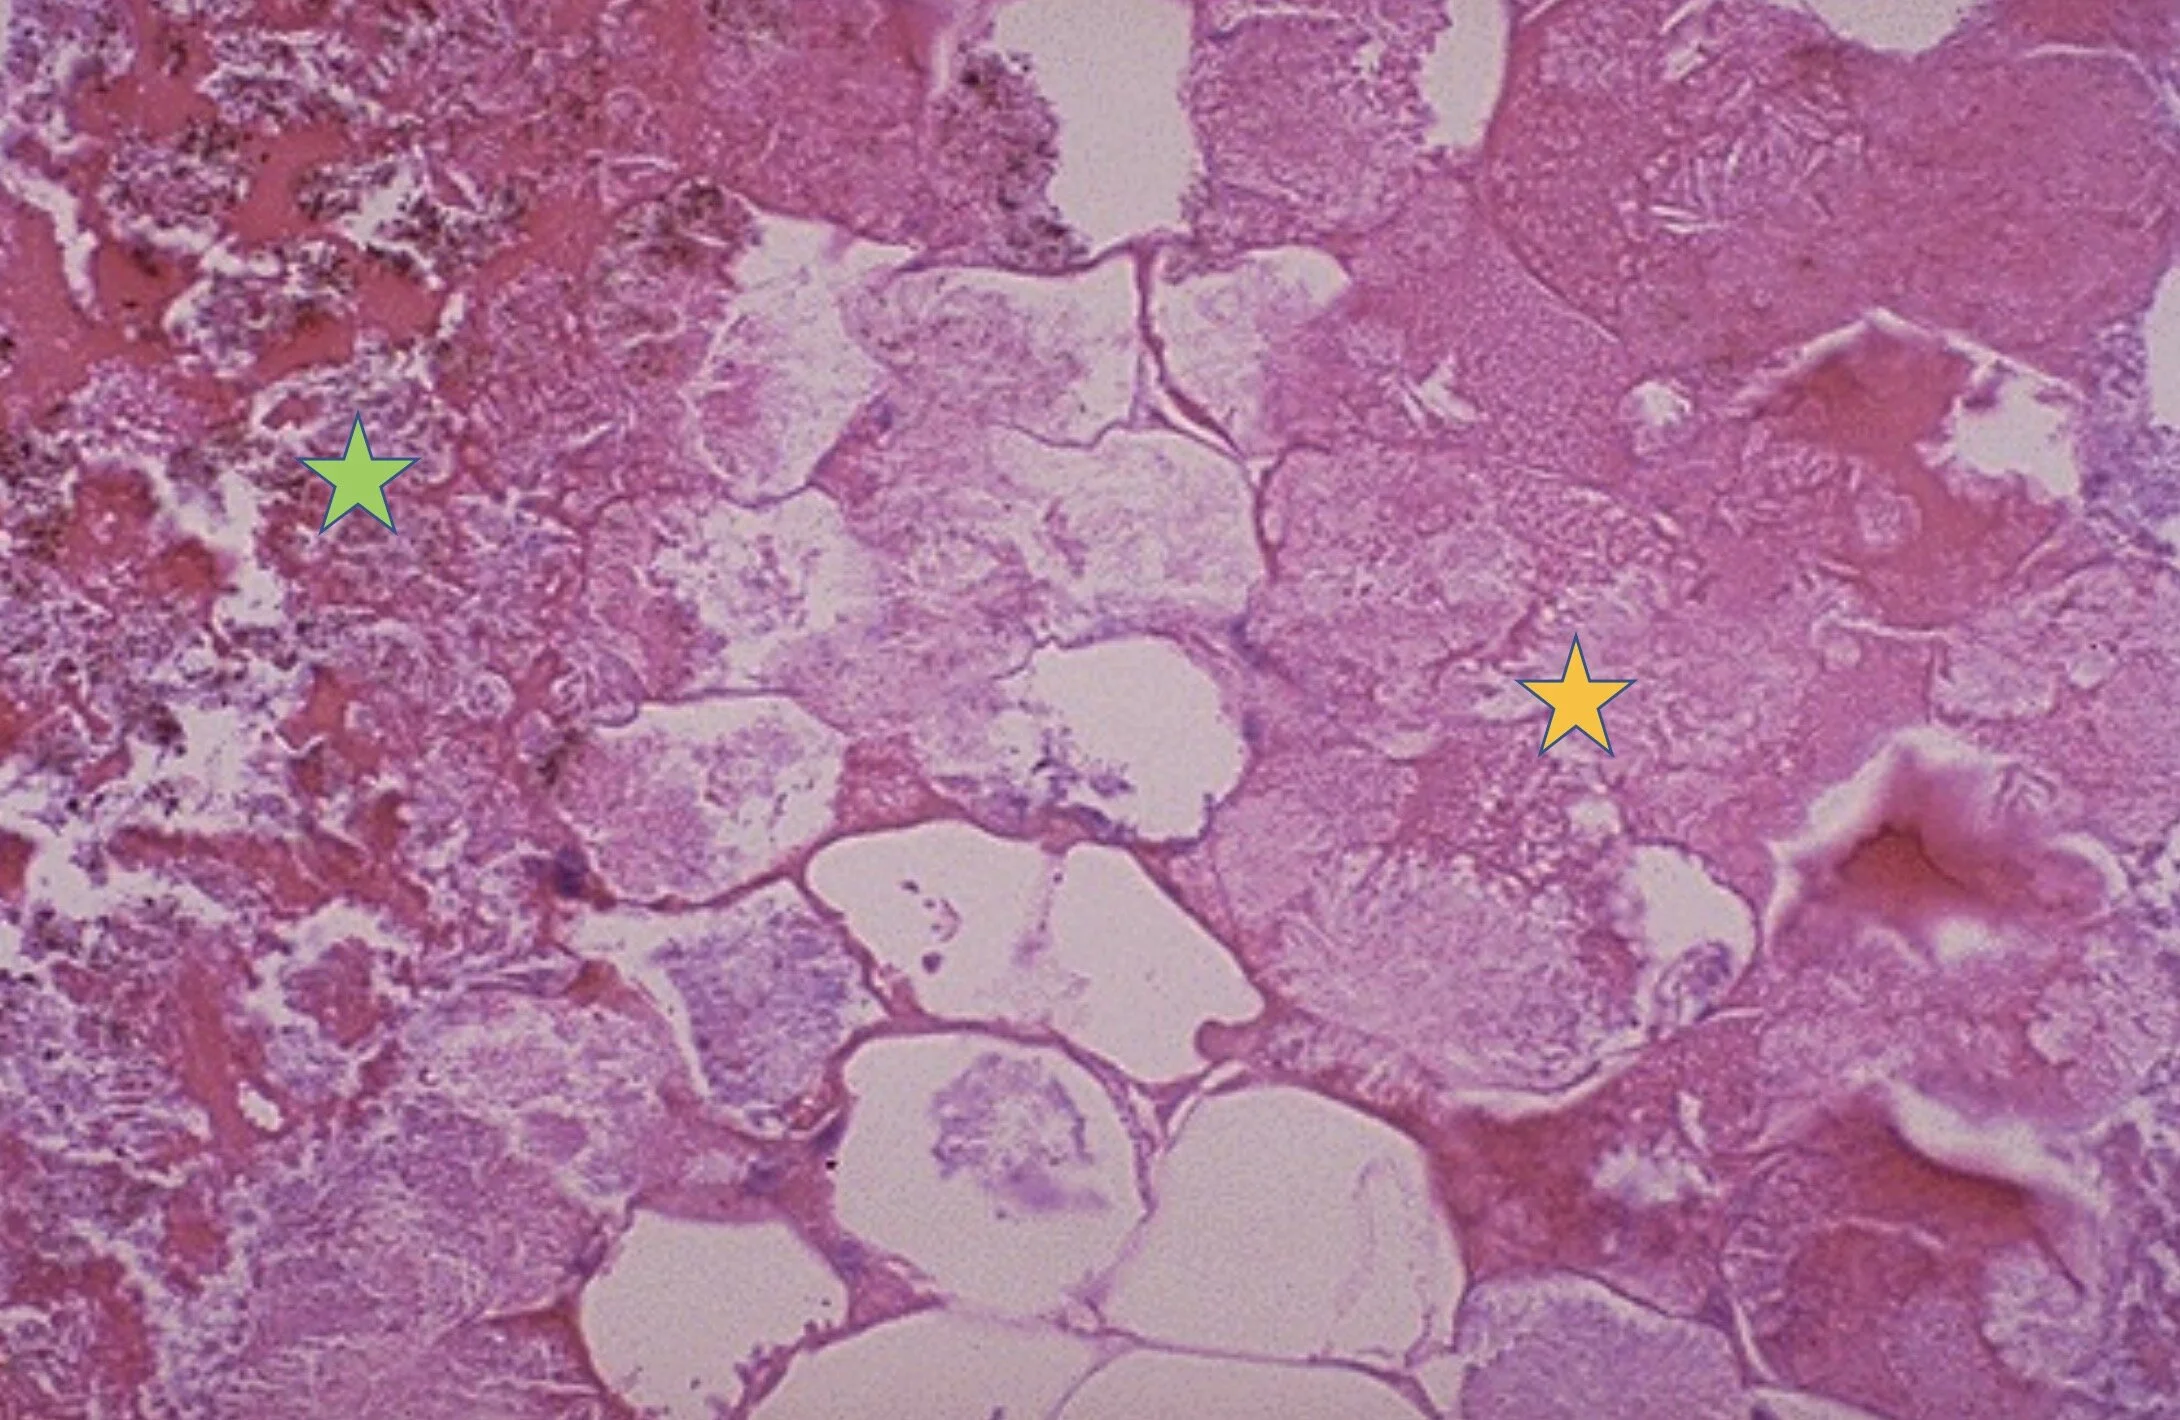

Three Types Of Fat Necrosis Damaged cells release lipases, which split the triglyceride esters within fat cells. Fat necrosis has three stages of evolution. There are different types of fat necrosis, including: Damaged cells release lipases, which split the triglyceride esters within fat cells. This can lead to local cyst formation with or. Chalky, white areas from the. Learn about the different types of necrosis, such as coagulative,. This occurs due to injury or trauma to the fatty. It may be easier to diagnose superficial fat necrosis using imaging than fat necrosis in nonsuperficial sites and avoid biopsy for several reasons. Necrosis is the death of your body tissue due to various factors. First, the location of the lesion is. See this in acute pancreatitis. The first stage is characterized by disruption of adipocytes following an inciting event. Lipomembranous fat necrosis (lfn) is an uncommon but distinct form of fat necrosis, which is characterized by eosinophilic,.

Fat Necrosis Histology Three Types Of Fat Necrosis There are different types of fat necrosis, including: Chalky, white areas from the. The first stage is characterized by disruption of adipocytes following an inciting event. Damaged cells release lipases, which split the triglyceride esters within fat cells. Lipomembranous fat necrosis (lfn) is an uncommon but distinct form of fat necrosis, which is characterized by eosinophilic,. See this in acute. Three Types Of Fat Necrosis.